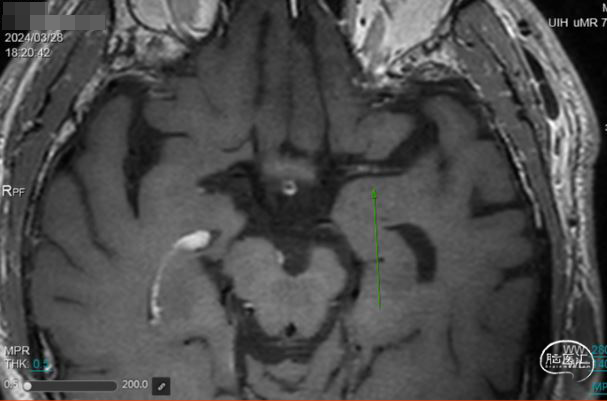

➢ 头颅MRI

左侧顶枕叶陈旧性梗塞,未见新发梗塞病灶。

➢ 头颅高分辨磁共振

管壁高分辨磁共振提示闭塞段斑块有强化,闭塞段不长。